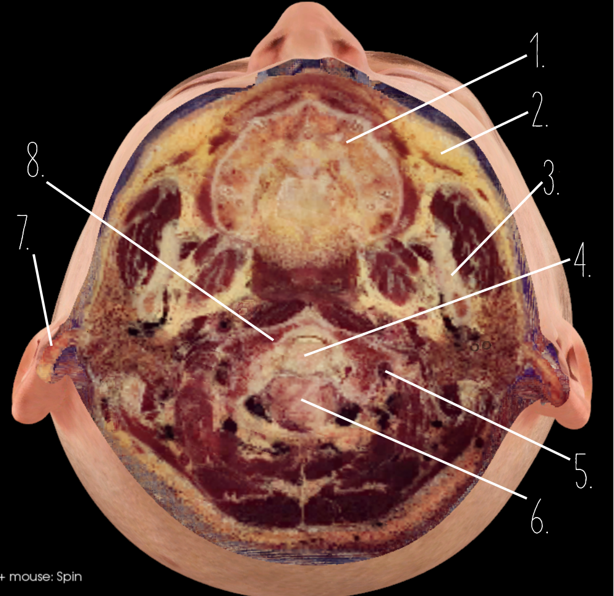

1?

Nasal Bone

2?

Maxillary Sinus

3?

External Acoustic Meatus

4?

Pons

5?

Cerebellum

6?

Mastoid Air Cells

7?

Mandibular Condyles

8?

Sphenoid Bone

9?

Maxillary Bone